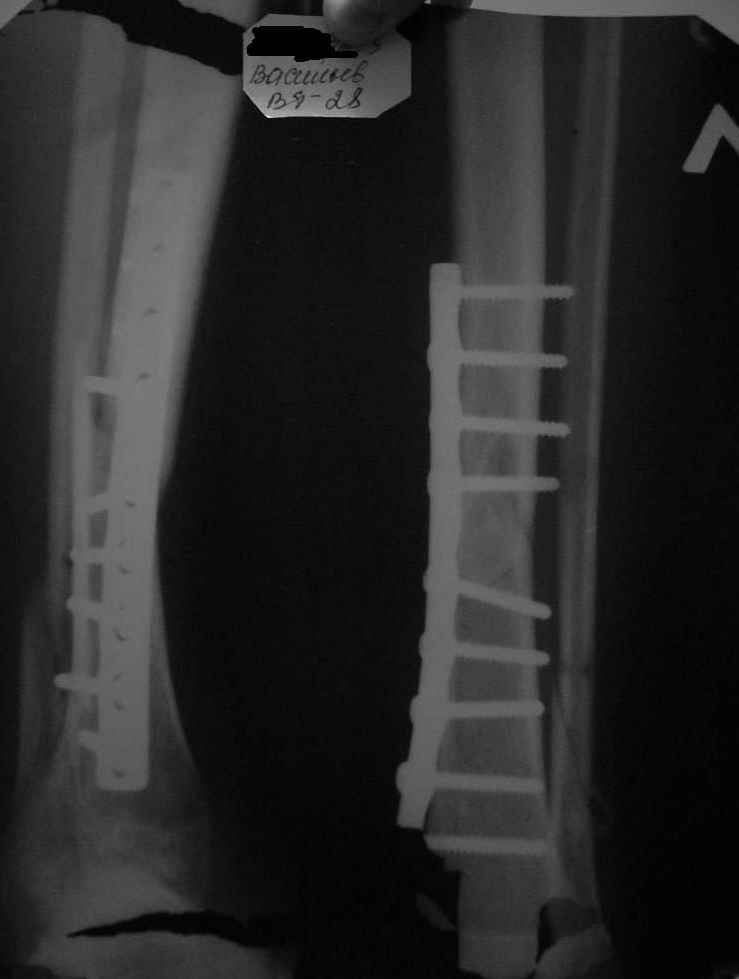

Перелом н/3 обеих костей голени, неправильный остеосинтез

Мне 28 лет. Травма 13.12.08 - перелом н/3 обеих костей голени при неудачном приземлении с парашютом; 17.12.08 выполнен остеосинтез б/б кости пластинкой; 17.03.08 - снят гипс, сращение имеется. Только через 3 месяца после операции выяснилось, что операция сделана криво - имеется смещение в боковой проекции. Сейчас прохожу восстановительное лечение, боли в области перелома отсутствуют. Подскажите пожалуйста, как быть? Оставить всё как есть или ломать по новой?P.S. Есть большое желание продолжить прыжки с парашютом.

Рентгенограмма когда сделана?

Покажите сегодняшние снимки.